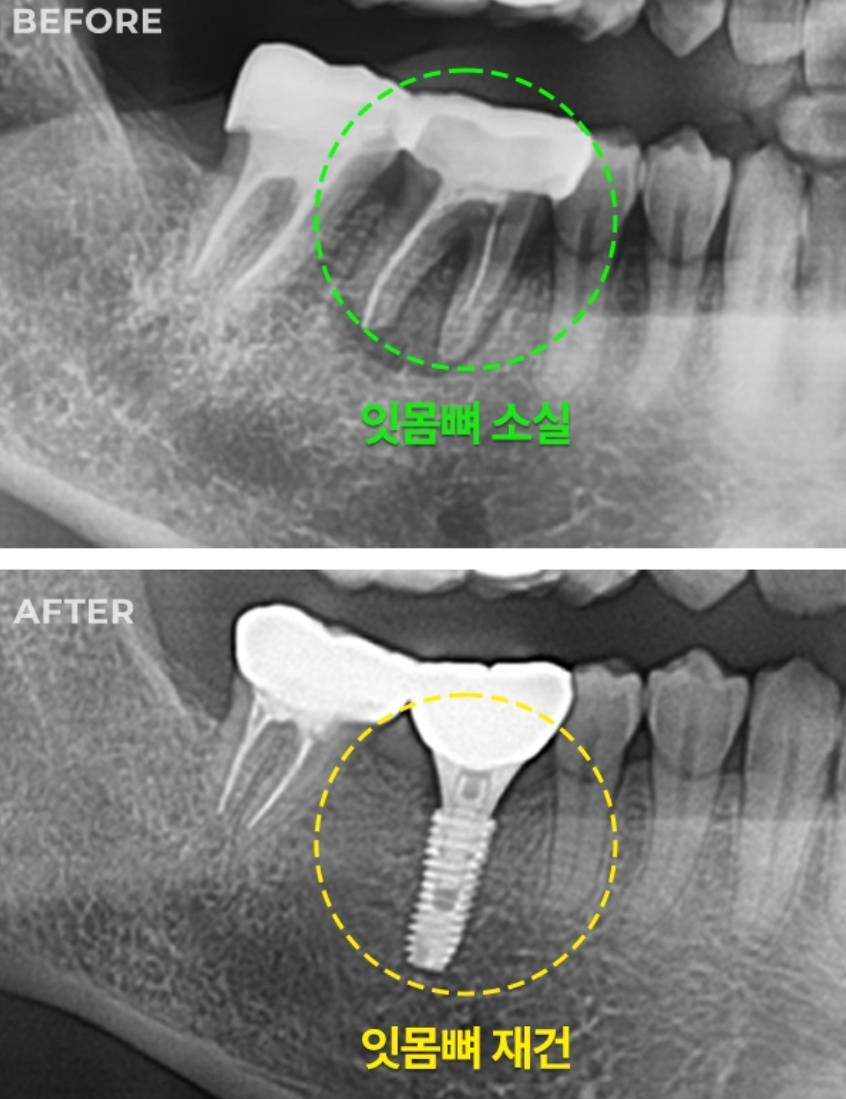

미사랑치과는 26년 넘는 임상 경험을 가진 구강악안면외과 전문의가 꼼꼼하게 진료하는 곳으로 유명하데이. 특히 임플란트는 3D CT로 정밀 진단하고, 뼈 이식이나 어려운 케이스 임플란트도 자신있게 한다 카네. 턱관절 치료도 전문적으로 하고, 환자 상태에 따라 맞춤 스플린트도 제작해 준다카니 믿음이 간데이.

임플란트 수술 과정을 보호자용 태블릿으로 보여줄 수 있다 카고, 3D 맞춤 보철로 자연치아처럼 정밀하게 만들어준다 카니 더 믿음이 가네. 오스템 임플란트 사용하고, 임플란트 비용도 합리적인 편이라 하니, 임플란트 고민 있는 분들은 상담 받아보이소.